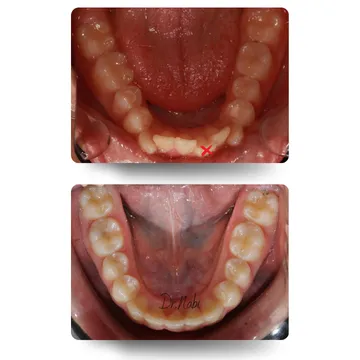

در این بخش تعدادی از کیسهای واقعی درمان شده با ارتودنسی نامرئی رو میبینی. تصاویر قبل و بعد، میزان نامرتبی دندونها، نوع اصلاح انجام شده و مدت زمان درمان به صورت خلاصه نمایش داده شده. تمامی درمانها تحت برنامه ریزی تخصصی دکتر نبی و با پیگیری مستمر انجام شده، تا علاوه بر بهبود زیبایی لبخند، پایداری نتیجه نیز حفظ بشه [2].

این خانم عزیزمون، به دلیل نامرتبی نسبتا شدید و کمبود فضا، یک دندان جلویی فک پایین کشیده شد و درمان با الاینرهای شفاف حدود یک سال طول کشید. قوس دندونها کمی وسیعتر شد و تمامی نامرتبیها به طور طبیعی اصلاح شدن.